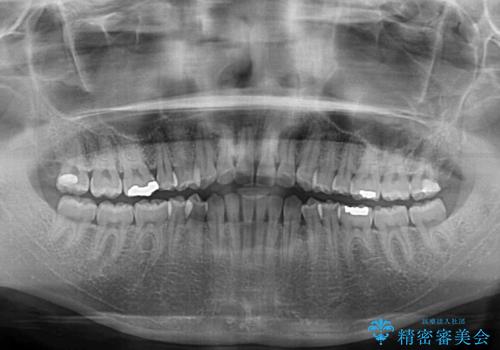

受け口傾向の前歯 すきっ歯の改善

- 前歯の隙間と口元の突出感を気にして来院された患者様です。

嚥下時に舌を突出させる癖があり、成長期に下顎が有意に成長し、歯と歯の間に隙間ができてしまいました。

舌の癖を改善し、インビザラインにて治療を行うこととしました。

舌癖を改善したことで、隙間や突出感を改善することができました。

隙間は後戻りしやすいため、舌側を細いワイヤーで固定することとしました。